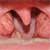

The first stage of diphtheria can cause a sore throat and inflammation of the throat tissues. Along with this discomfort comes along with a cough and head cold often with an increase in temperature.As the disease progresses people find it increasingly difficult to breathe.If left untreated victims of diphtheria can eventually die of lack of oxygen due to a film of membrane that grows over the opening to the airway at the back of the throat. This sheath usually spreads from around the tonsil site of one side to the tonsil on the other side.